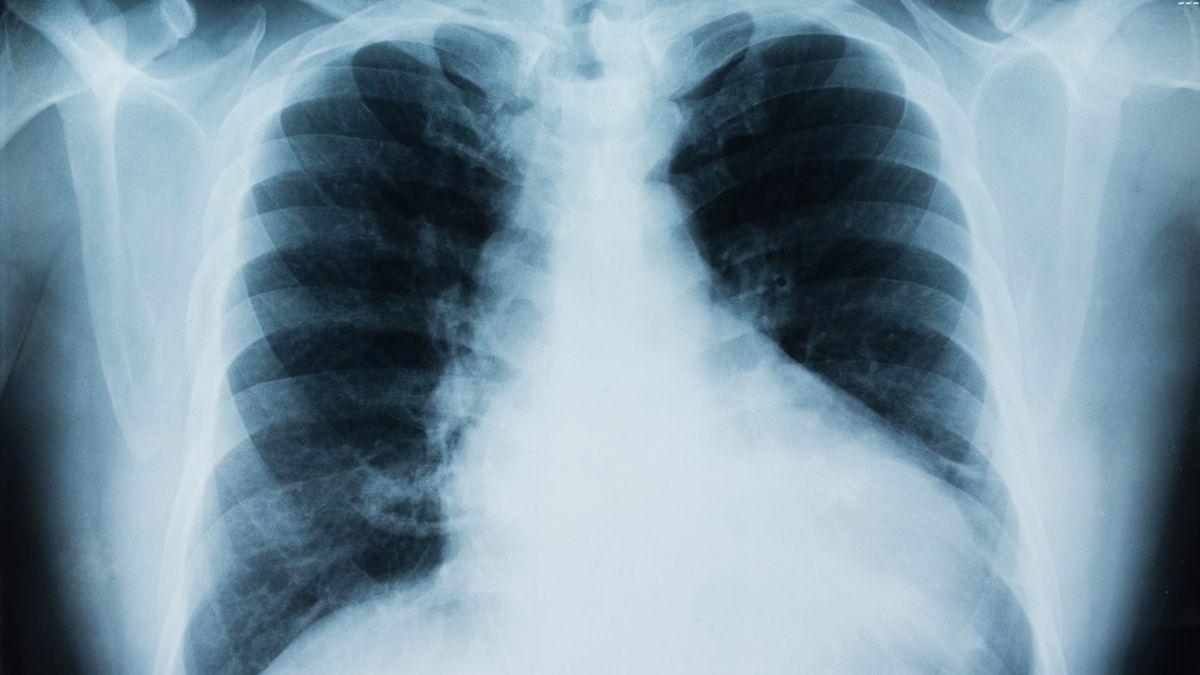

Rak płuc jest jednym z najczęstszych nowotworów złośliwych na świecie i stanowi poważne zagrożenie zdrowotne. Specjaliści nieustannie apelują o świadomość tej choroby, a nawet na paczkach papierosów można znaleźć przerażające ilustracje przedstawiające jej konsekwencje.

Każdego roku rak płuc przyczynia się do śmierci 1,3 miliona osób na całym globie, co czyni go jednym z najbardziej śmiertelnych nowotworów.

Szanse na wyleczenie w dużej mierze zależą od wczesnej diagnozy, ponieważ im szybciej wykryta choroba, tym większa możliwość zapobiegania przerzutom do innych narządów. Niestety, wielu chorych trafia do lekarza dopiero w zaawansowanym stadium, co często wynika z braku wiedzy na temat wczesnych objawów raka płuc.

Rak płuc to jeden z najgorzej rokujących nowotworówRak płuc to jeden z najgorzej rokujących nowotworów